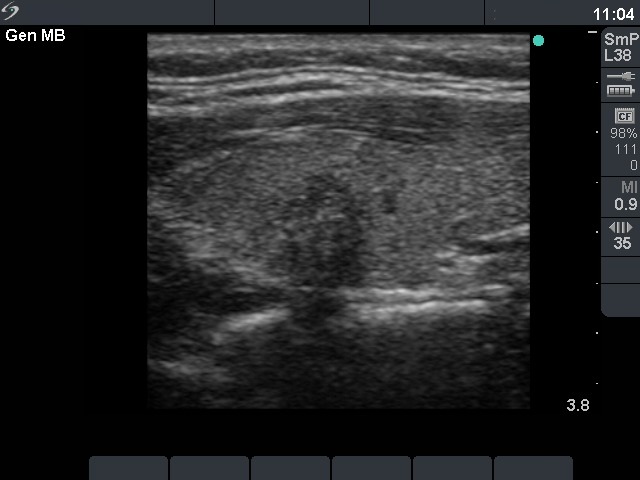

Ultrasonography: the thyroids were echonormal. There was a small moderately hypoechogenic lesion in the left lobe. The nodule displayed microcalcifications and had blurred borders.

The ultrasound pattern was suspicious for a papillary cancer. The combination of hypoechogenicity, irregular borders, the presence of microcalcifications and the taller-than-wide sign increased the risk of malignancy to more than 10-fold. In our minimally-moderately iodine deficient region, it means that instead of a 2.2% risk the patient had a 25% risk for malignancy.